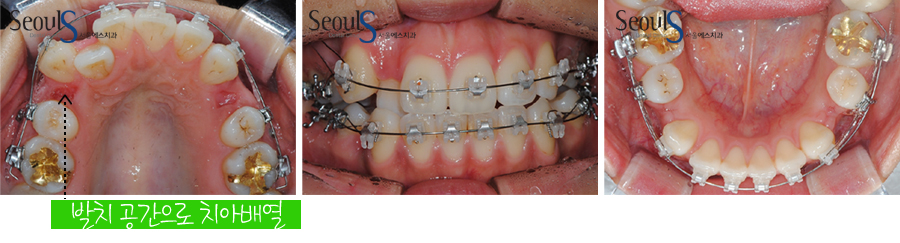

교정치료를 하는 과정입니다

교정 발치를 통해 발치 공간으로 어긋나있는 치아를 배열합니다

교정용 미니스크류를 이용하여 왼쪽으로 틀어져 있는 치아들을 이동시켜 중심선을 맞추면서

발치 공간을 모읍니다

발치 공간이 다 모이면 윗니와 아랫니가 잘 물릴 수 있도록 조정합니다

유지 장치를 연결하였고 교정치료는 마무리되었습니다